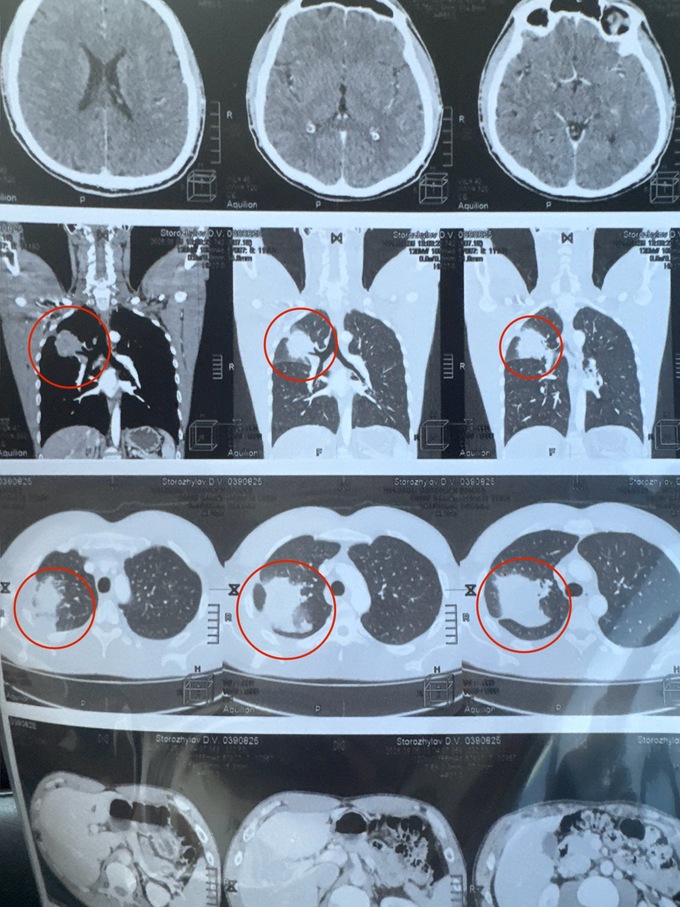

Бывший капитан сборной Украины по волейболу Дмитрий Сторожилов борется с онкологическим заболеванием. Чтобы пройти курс срочного лечения в Германии, требуются немалые средства. По результатам медицинских обследований у Дмитрия обнаружено новообразование в верхней части правого легкого с высокой вероятностью злокачественного процесса. Размеры образования – 62×55×60 мм.